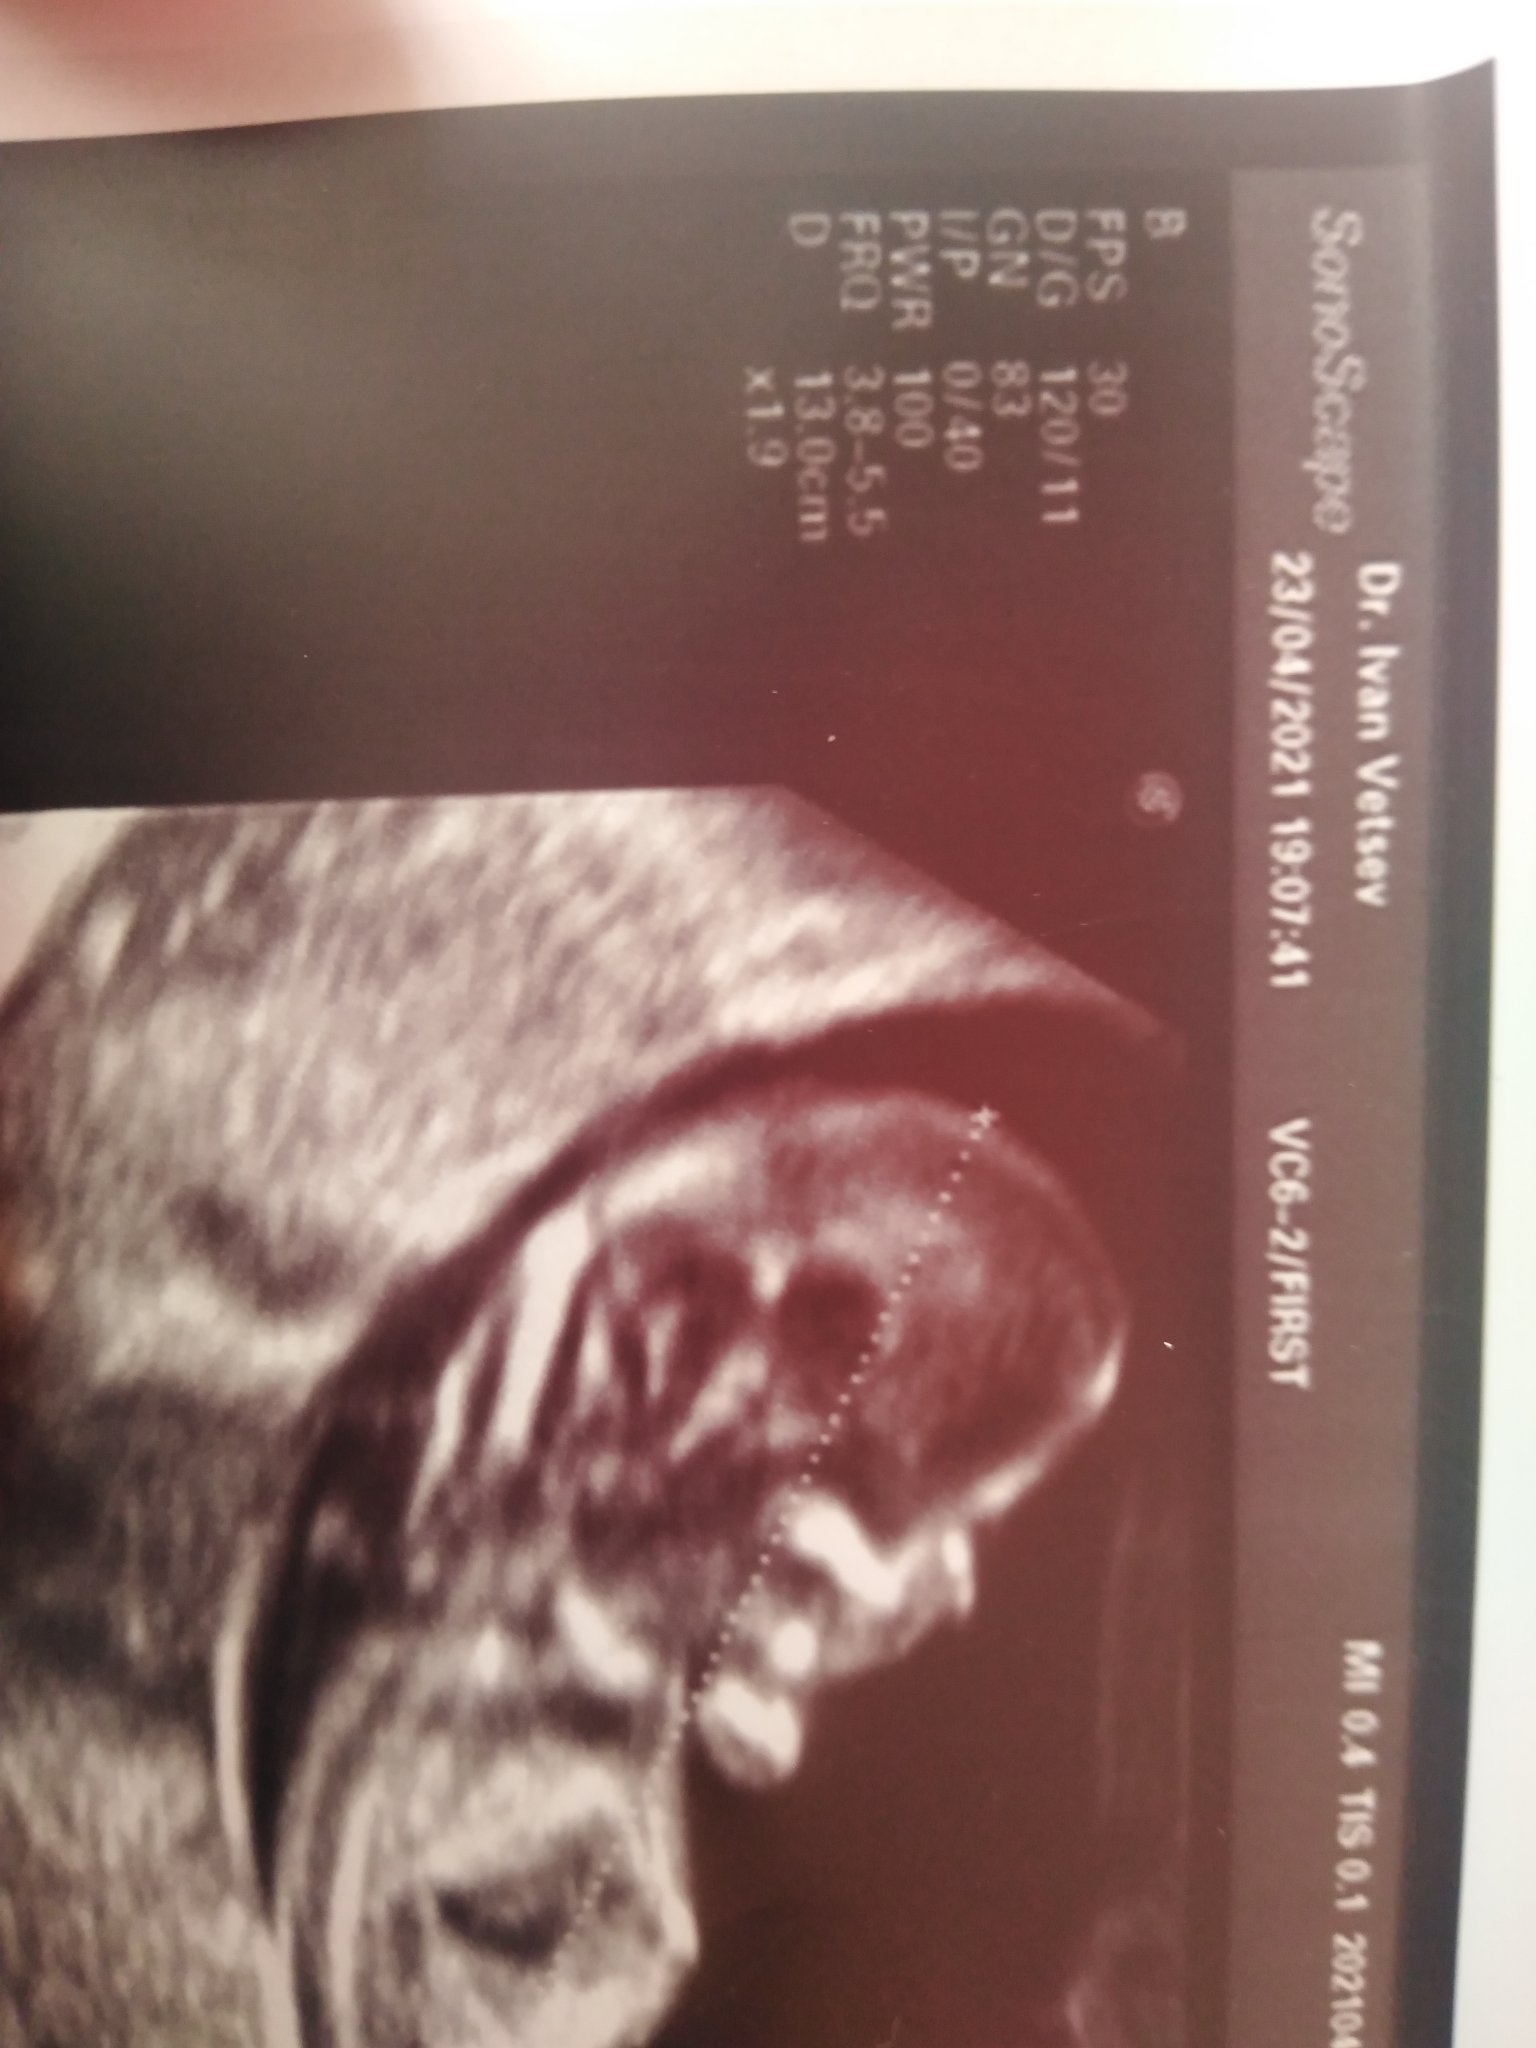

Това е снимката с 13 см

На двете снимки показва 10 см на другата 13

Зависи как е застанало бебчето, защото по принцип седят малко сгънати, а за измери хубаво доктора издържава с няколко см самата снимка.

ПП: аз и на дветехснимки виждам 10см